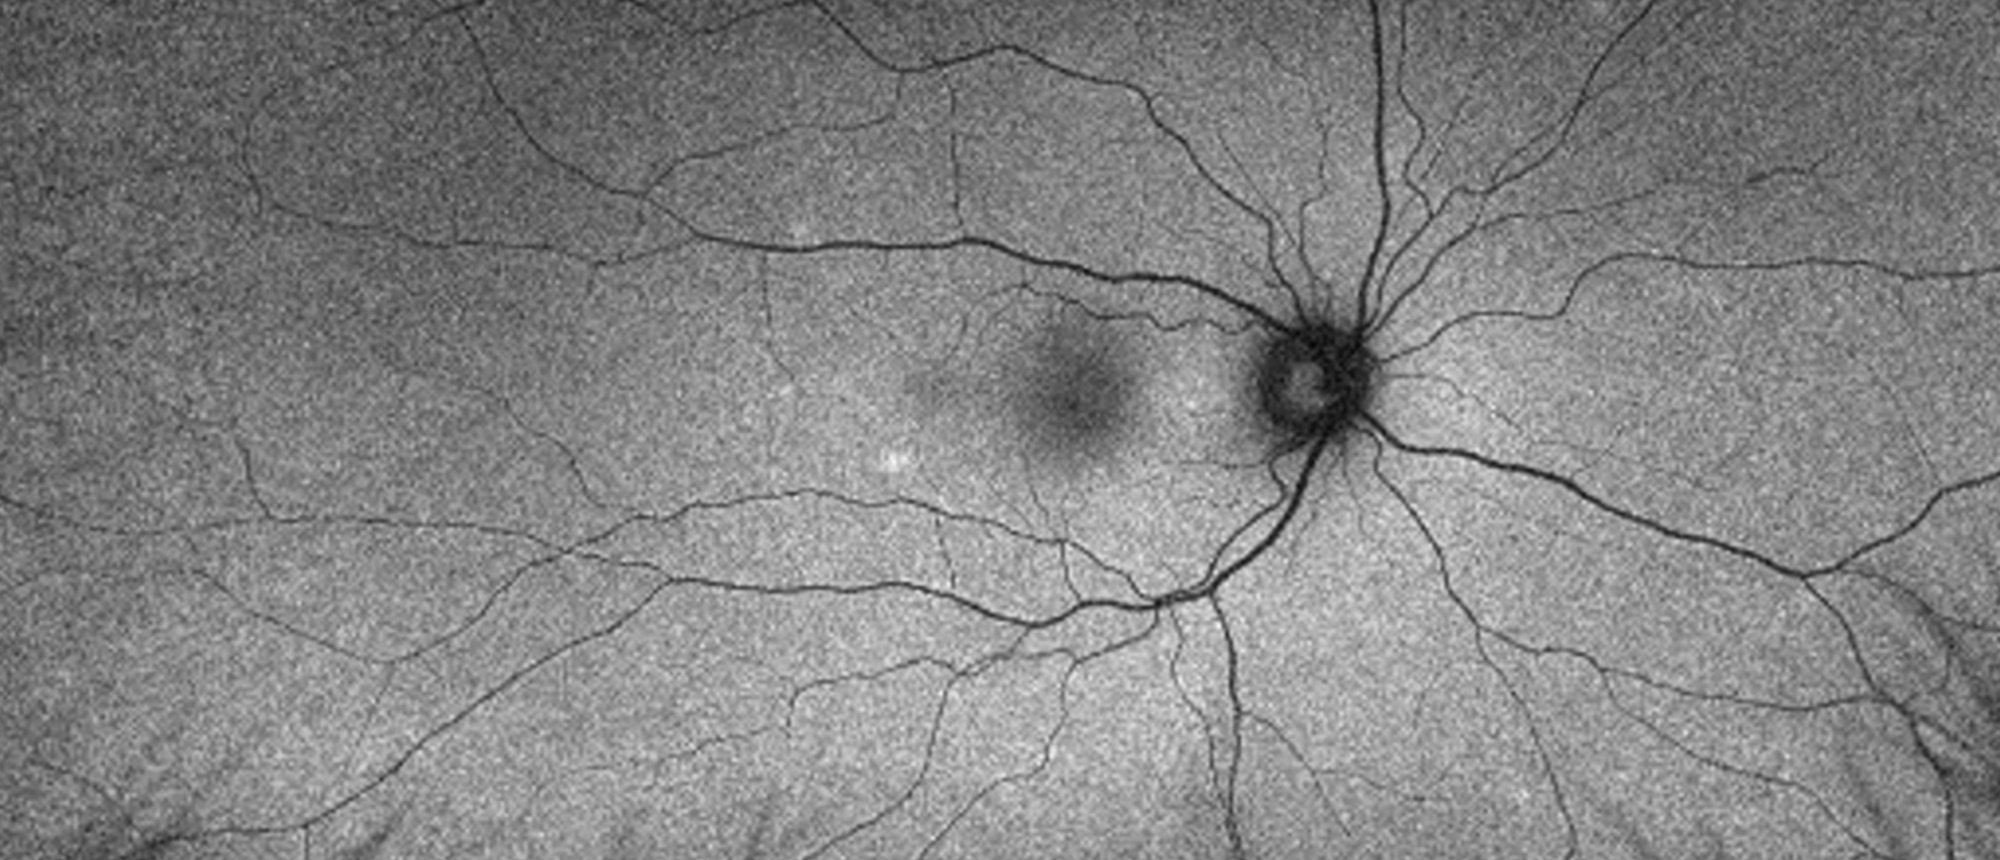

Pachyphakia, Microcornea, and Angle Closure Following Laser Treatment of Retinopathy of Prematurity

A patient who had been previously treated with retinal photocoagulation for severe retinopathy of prematurity. Ultrasound biomicroscopy revealed nearly spherical, thickened lens with complete angle closure. Fundus photography with diffuse chorioretinal scars consistent with previous photocoagulatio…